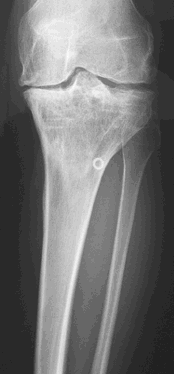

Hier ist schön sichtbar, wie die Gelenksachse korrigiert wurde